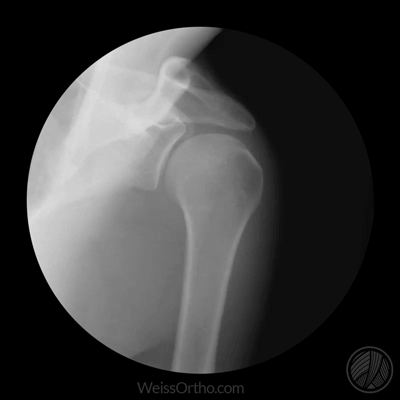

Met X-rays of Röntgenstralen kunnen we in ons lichaam kijken, maar we kennen het meestal gewoon als een foto: een stilstaand beeld van botten of gewrichten. Door fluoroscopie kunnen echter ook bewegende beelden gemaakt worden.

Ontwerper en fotograaf Cameron Drake ging aan de slag met beelden van het orthopedisch instituut van Dr. Noah Weiss in de V.S. (Weis Orthopaedics). Op zijn blog legt Drake uit hoe hij de beelden die Dr. Weiss gemaakt heeft van zijn patiënten omgezet heeft in deze gifs.